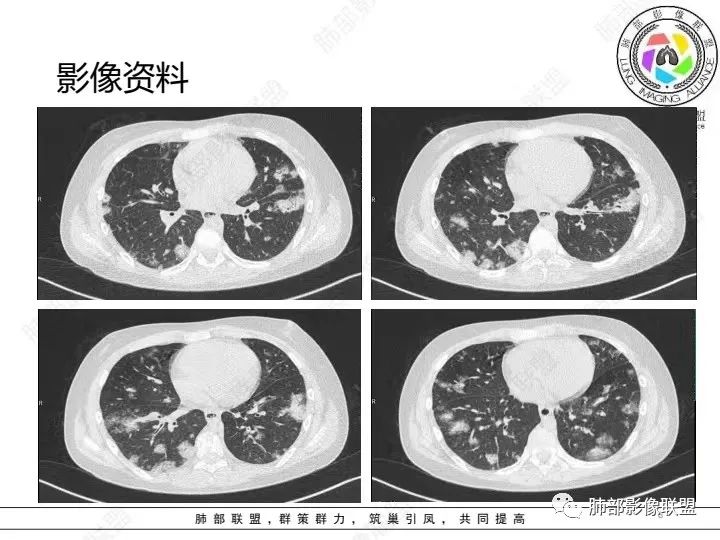

【病例】血源性金黄色葡萄球菌性肺炎1例CT影像

1.男性少年儿童,外伤后髋部疼痛,畏寒发热、咳嗽、呼吸困难。

休克血压。CRP、PCT明显升高。血气为代谢性酸中毒、呼吸性碱中毒。

2.影像上肺多发混合密度片影,随机分布,胸膜下分布优势,病灶边界大多隐约可辨,偏柔和,动脉血管影穿行,未见钙化、液化空洞、或明确气囊影,未见树芽征。

3.双侧胸腔未见积液。双肺门及纵隔未见增大淋巴结。

4.肝左右叶密度减低,未见结节影、块影或液化区。

3.影像方面:双肺多发病灶,随机分布,且有相当部分沿胸膜下,是可以符合血流感染的。

4.责任病原菌:注意是儿童。孩童易外伤,易感染,皮肤粘膜感染、骨关节感染(如急性骨髓炎)是比较常见的,金葡菌感染是多见的,脓毒血症也以金葡为先。只是没有短期复查对比影像资料,不能观察到有无快速出现的气囊影或脓胸等(快速出现的气囊影尤具特征性)。